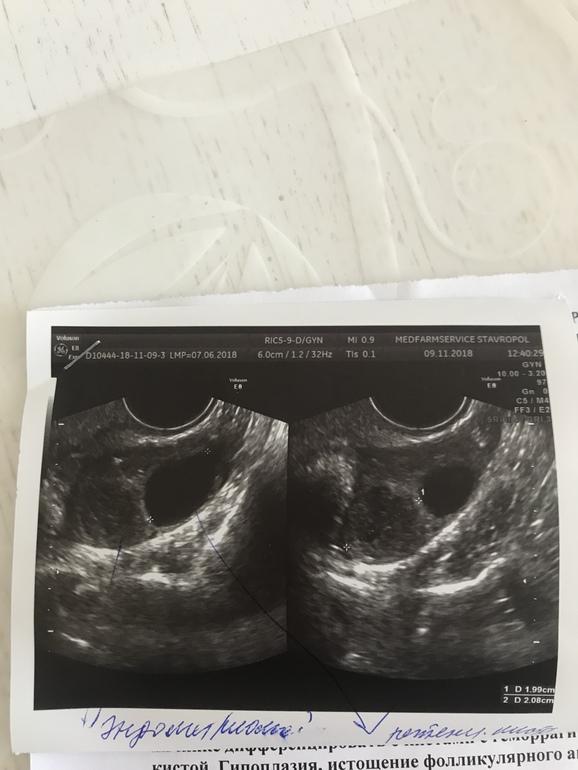

На УЗИ мне сказали: в правом яичнике 5 мелких фоликов, но тоже как бы под сомнением и что у меня там снова киста эндометриодная и ретенционная я в шоке! Теперь сижу и думаю ... не могла она чего напутать узистка ?! Она уверяла меня, что после визанны овуляция вообще не возможна..а я как ту почитала, что у многих сразу после отмены визанны она была и даже девочки...Помогите советом кто может, кто разбирается в снимках УЗИ 🙏У кого случались ошибки подобного рода?

Возможно перепутать кисту с фолликулом?